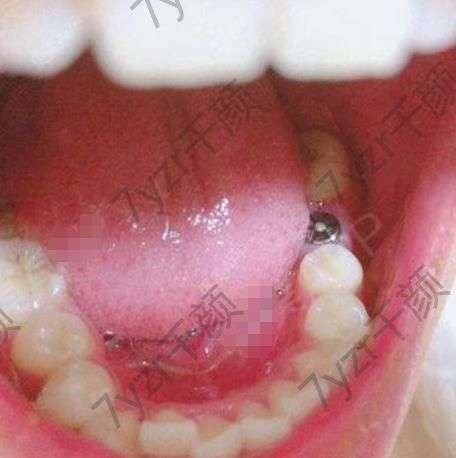

去醫(yī)院面診完已經(jīng)有半個(gè)月的時(shí)間了。因?yàn)樽约汗ぷ魈貏e忙,一直沒(méi)有時(shí)間去做手術(shù)。所以又拖了這么長(zhǎng)時(shí)間。今天終于把我的牙給種上了,醫(yī)院的護(hù)士都特別的溫柔。醫(yī)院的環(huán)境也特別的好。進(jìn)入手術(shù)室時(shí),醫(yī)生給我打上麻藥,之后很快就進(jìn)入了手術(shù),手術(shù)全程大概用了四十多分鐘的時(shí)間。手術(shù)過(guò)程中沒(méi)有太強(qiáng)烈的疼痛感。出了手術(shù)室又等了半個(gè)小時(shí),醫(yī)生觀察了一下我傷口的情況,確定沒(méi)有問(wèn)題之后告訴我可以回家了,七天之后再回醫(yī)院進(jìn)行拆線(xiàn)。

我的牙樁已經(jīng)種上三天的時(shí)間了,現(xiàn)在沒(méi)有特別強(qiáng)烈的疼痛感了,吃飯可以正常的吃了,只是不能用種牙的那一邊。現(xiàn)在我還不能吃一些刺激性的東西,太辣,太涼,太熱,太硬的東西都不可以吃。昨天一個(gè)好兄弟,剛剛從外地過(guò)來(lái),還說(shuō)和我出去喝點(diǎn)酒。但是因?yàn)槲椰F(xiàn)在還在忌口,所以沒(méi)能去,因?yàn)槿チ酥蟊苊獠涣司褪呛染屏?,而且我們?cè)谝黄鹂隙ㄒ矔?huì)點(diǎn)一些。不應(yīng)該吃的東西。我還是自己在家再堅(jiān)持吃幾天清淡的飯菜吧。

已經(jīng)一周的時(shí)間了,現(xiàn)在也沒(méi)有什么特別的感覺(jué)了,今天早起就接到了醫(yī)院的電話(huà),提醒我回醫(yī)院進(jìn)行拆線(xiàn)。到了醫(yī)院之后醫(yī)生已經(jīng)在等待著我了醫(yī)生檢查了一下我種植的牙樁說(shuō)恢復(fù)的很好。然后醫(yī)生就給我安排了拆線(xiàn)。醫(yī)生說(shuō),種完牙樁之后還要等一個(gè)多月才能把那顆牙種上。之前因?yàn)檫@個(gè)牙窟窿吃東西的時(shí)候特別難受,馬上我的這顆牙就要種好了。想想一下,以后吃東西都不礙事了。

現(xiàn)在我的牙已經(jīng)沒(méi)有什么特別的感覺(jué)了,傷口恢復(fù)的也很好。醫(yī)生說(shuō)只能等我的牙齦的骨頭和種植體長(zhǎng)到穩(wěn)定的狀態(tài)之后,才能裝上牙冠。我現(xiàn)在時(shí)不時(shí)的就會(huì)用我的舌頭去碰一下牙樁。感覺(jué)還有些不適應(yīng),不過(guò)我相信再等待一段時(shí)間肯定就會(huì)慢慢適應(yīng)的,我還尋問(wèn)醫(yī)生大概多久可以適應(yīng)下來(lái),醫(yī)生說(shuō)大概需要三個(gè)月的樣子,其實(shí)我感覺(jué)三個(gè)月說(shuō)長(zhǎng)也不長(zhǎng),說(shuō)短也不短,實(shí)在是太難熬了。

前幾天去醫(yī)院復(fù)查的時(shí)候,醫(yī)生說(shuō)在恢復(fù)一周的時(shí)間就可以給我裝上牙冠了,裝上牙冠之后如果不是特別硬的東西都可以吃了,實(shí)在是太開(kāi)心了,種植完這一顆牙之后,我一定要好好得保護(hù)我的牙齒。